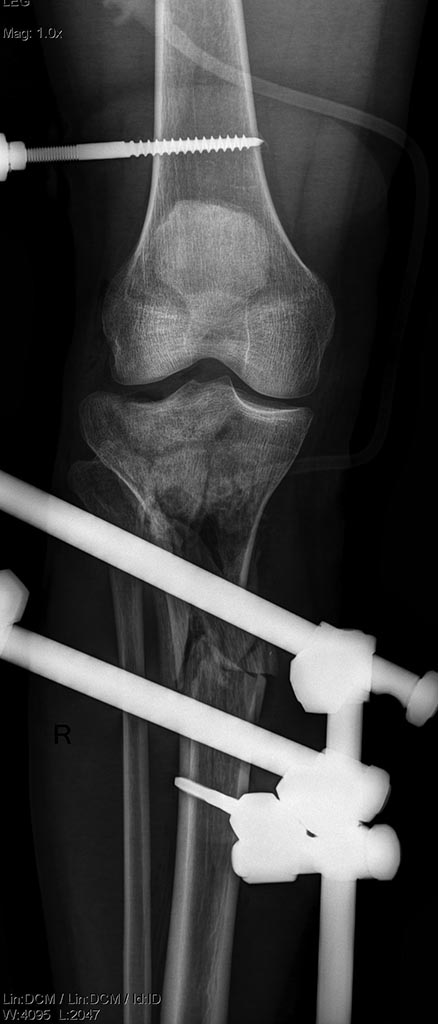

Уважаемые коллеги! Поступила пациентка после получения травмы в

результате столкновения с препятствием.

Открытые (3a-b) оскольчатые внутрисуставные переломы проксимального

отдела обеих костей правой и левой голени. (см. снимки)

При поступлении выполнено: ПХО открытых перелом костей правой и левой

голени, фиксация в аппаратах; фиксация перелома левой бедренной кости в

неосложненном заживлении, остеосинтез правой большеберцовой кости

пластиной; остеосинтез бедренной кости стержнем; локтевой кости